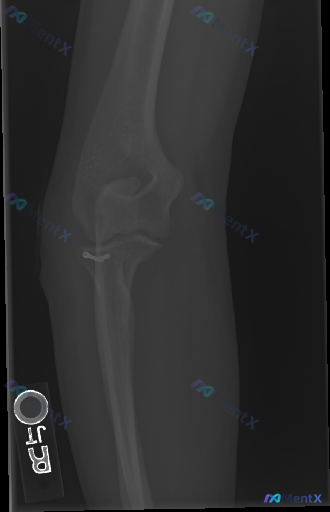

整理了一份肘关节术后的侧位X光影像分析资料,先不直接给结论,大家一起来看看读片思路。 影像基本情况 - 标记为左侧(L)肘关节侧位片 - 可见肱骨远端、尺骨近端的金属内固定系统(钢板、螺钉),还有串珠状高密度缝合钉影 - 术区有金属伪影干扰 - 局部可见骨密度增高区域(考虑骨痂形成迹象) - 目前未...